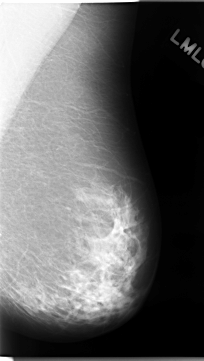

C_0034_1.LEFT_MLO

LEFT_MLO LINES 4688 PIXELS_PER_LINE 2648 BITS_PER_PIXEL 12 RESOLUTION 50 NON_OVERLAY